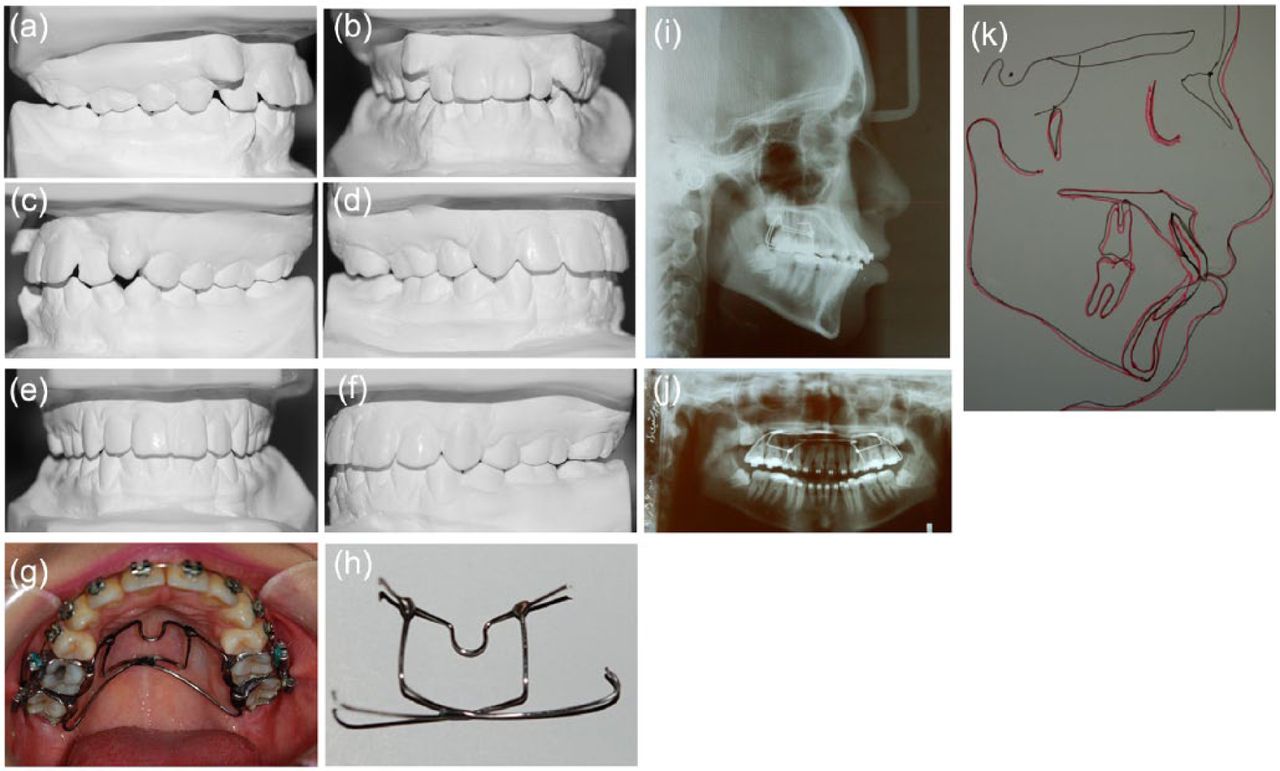

Figure 15.

Patient M.A. 16 years old, with a class I severe crowding problem: (a–f) study models before and after treatment; (g, h) butterfly arch when it is in place and when it is removed, respectively; (i, j) lateral cephalogram when the butterfly arch is in place; and (k) cranial base superimposition shows excellent control of anteroposterior and vertical dimensions during treatment although a little vertical growth is evident.